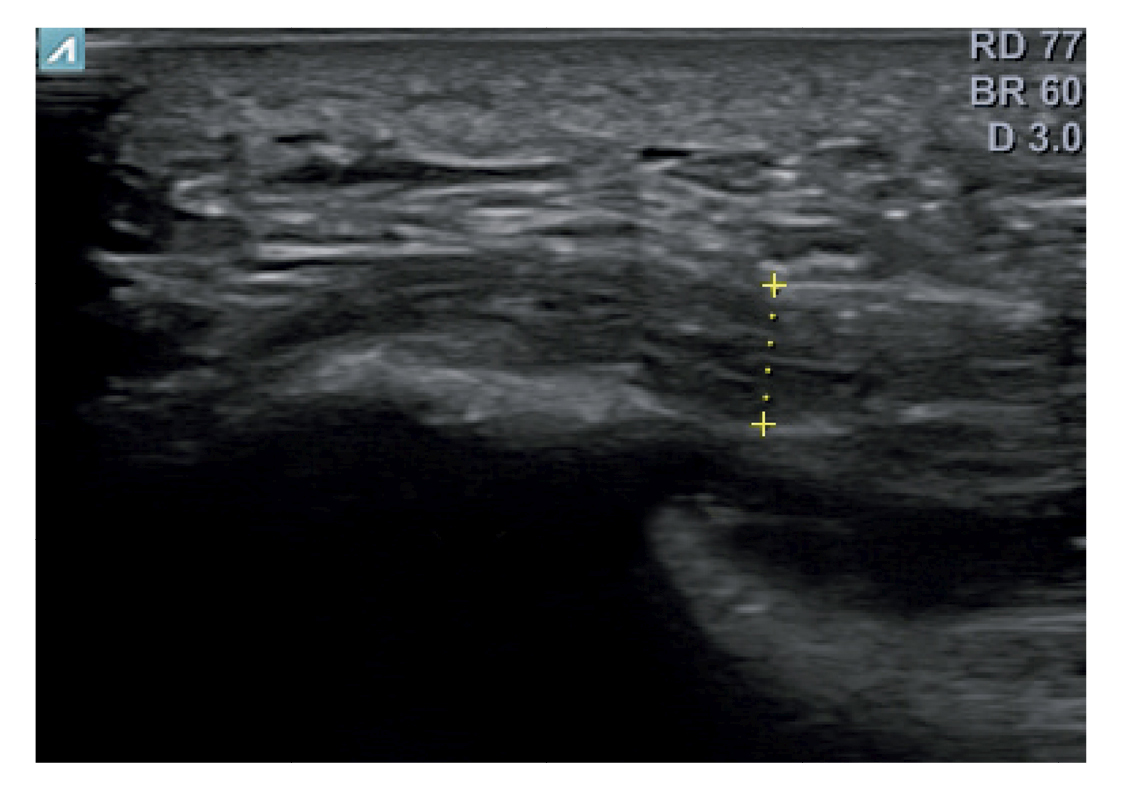

El diagnóstico se estableció en base a los síntomas y se confirmó mediante ecografía con equipo de alta resolución (Alpinion Ecube 9, ALPINION MEDICAL SYSTEMS Co., Ltd., República de Korea) con transductor lineal de 6 a 12 MHz (Figuras 2 y 3).

Figura 3. Área de medición del grosor de la fascia plantar. La línea punteada corresponde con la medición del grosor.